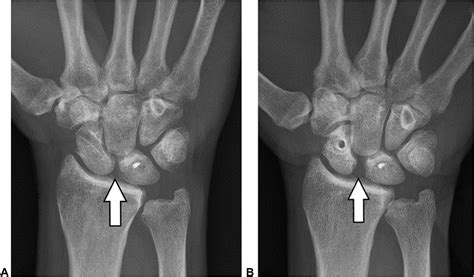

Diagnosing a Scapholunate Ligament Tear involves a combination of physical examination and imaging tests. The diagnostic process typically includes:

• Imaging Tests: X-rays, MRI, and CT scans can provide detailed images of the wrist, helping to confirm the diagnosis and assess the extent of the injury.